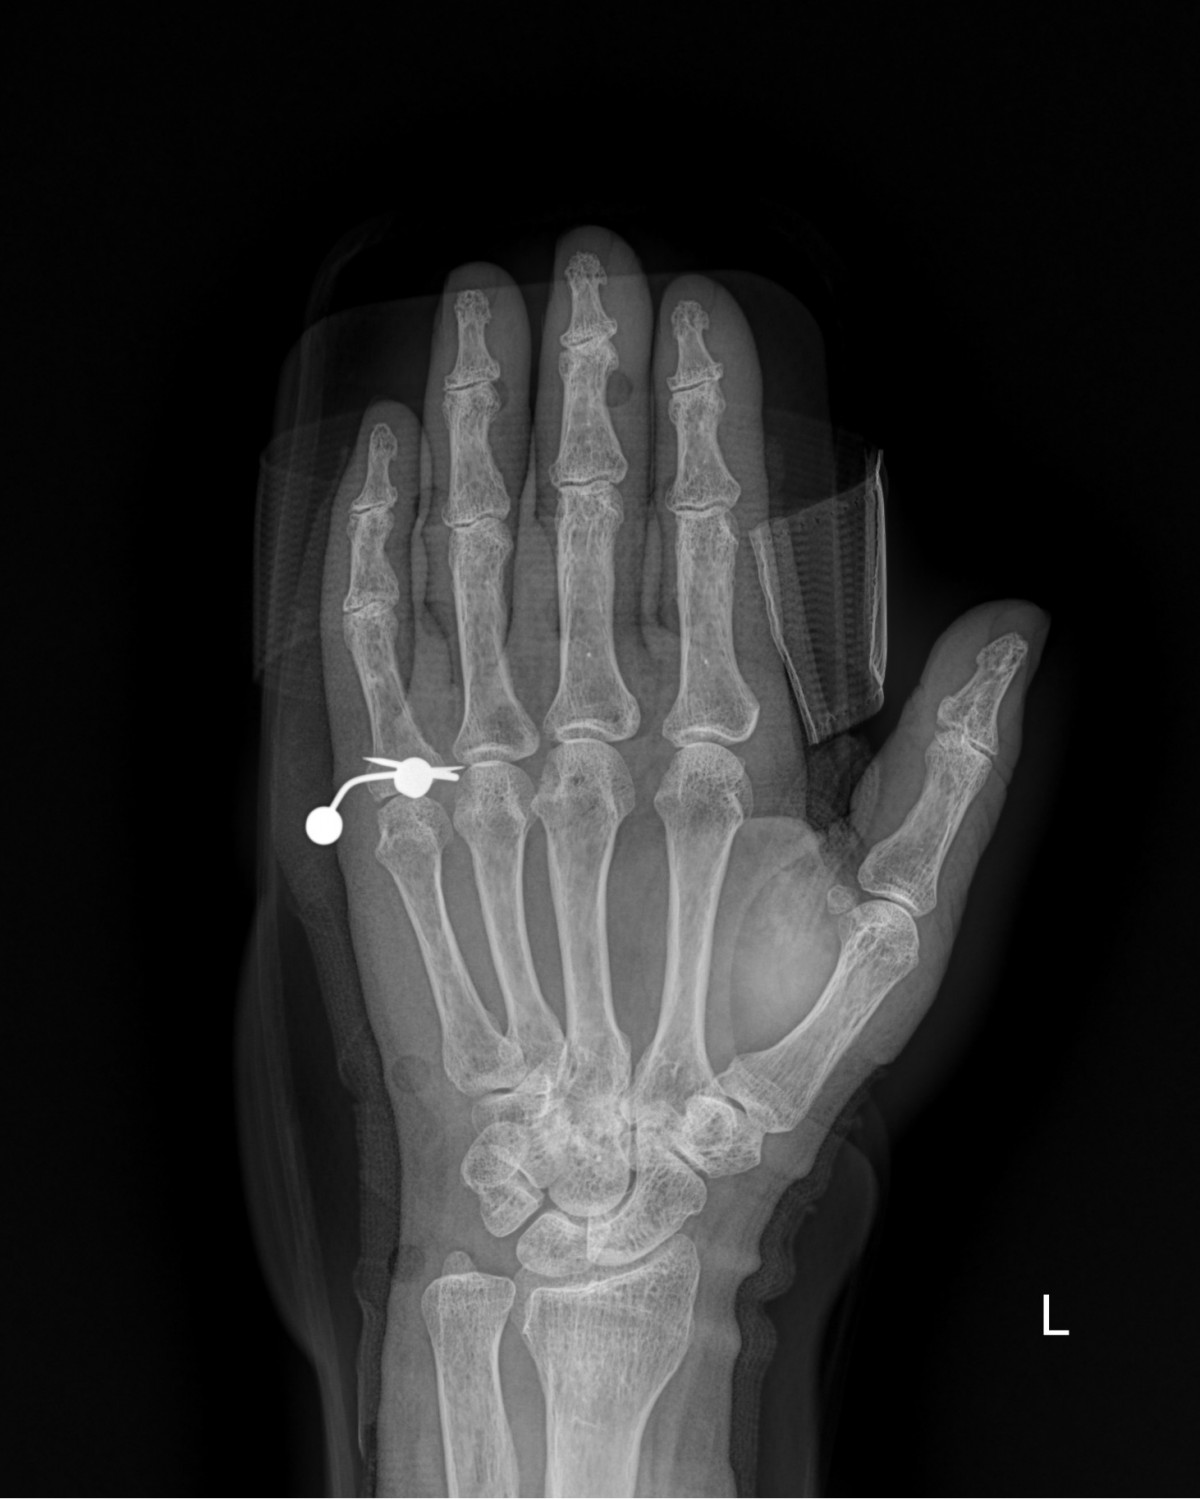

이재상원장님 손가락 골절 수술 안언O 환자

dae765e4d9ac96aee867c9d6292d8784_1758003465_4459.jpg